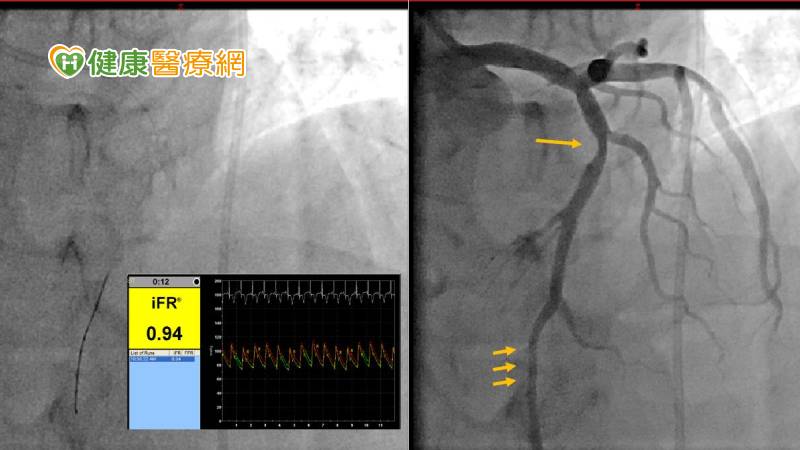

▲(右)江太太初步進行心導管檢查,顯示冠狀動脈多處狹窄(箭頭處),(左)接著進行iFR檢測,數值沒有顯著變化,暫時不用放置導管。(國泰醫院提供)

60歲的江太太患有糖尿病、高血壓、高血脂、十二指腸潰瘍,曾經因嚴重腸胃道出血而病危住院多日,今年更發現冠狀動脈中有廣泛的動脈硬化而且懷疑有嚴重狹窄!患者住院接受心導管的檢查,顯示冠狀動脈左前降支的中段及遠端都有約50-70%狹窄病灶,可能需要做血管擴張並置放冠狀動脈支架。但放了支架後,需要長時間同時服用2種抗血小板的藥物以避免支架內急性血栓,江太太擔心胃出血復發,而且平日沒有明顯心絞痛,希望好好地再度謹慎評估。心血管中心團隊使用即時冠狀動脈流速差iFR測量系統,以導絲進入血管量測左前降支在狹窄處前後的壓力差,數值顯示沒有明顯差異,暫時不需要置放支架。江太太在心導管檢查後,繼續積極服藥控制慢性病,經過多年仍沒有心絞痛,追蹤心臟的功能也在正常範圍。

然而,傳統上執行FFR需要耗費不少時間,注射藥物也常伴隨心臟暫時停止或者是支氣管收縮等副作用。隨著科技進步,目前研發出iFR系統量測技術,不需要注射藥物就可測量壓力,可免除藥物注射的副作用,檢查的時間也大幅縮短,能夠評估血管是否狹窄,精確找出哪些病灶才真正需要治療,避免放置多餘的支架,可以減少病患的經濟負擔,並且降低未來因為置放太多支架而增加再度狹窄的機會,以及長期服用抗血小板藥物所增加的出血風險。例如江太太曾經有過嚴重胃出血,如果血管內的病灶並沒有造成足夠的壓降,這時單憑導管影像決定置放支架,對於心臟缺氧可能沒有特別改善,而且置放支架之後,又要承受長期服用抗血小板藥物而增加的出血風險至少半年到1年。現今透過短時間的壓力量測,免除不必要的支架置放,對於同時有容易胃出血、腦出血等等的高風險病患,是相當有價值的。